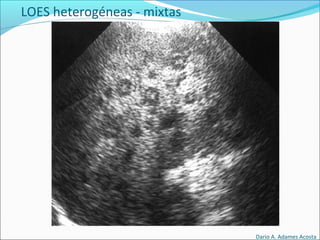

Lesiones básicas

LOES heterogéneas - mixtas

Dario A. Adames Acosta

• #57 Parasitos , tumoral , inflamatorio